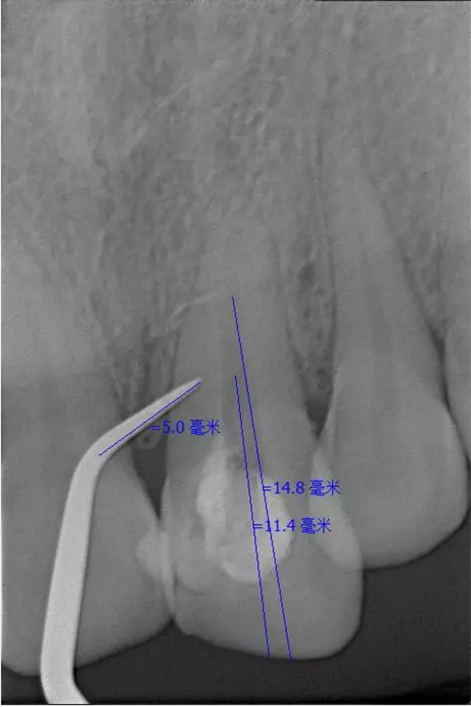

翻瓣去除側(cè)穿超出的牙膠尖

側(cè)穿超出的牙膠尖

術(shù)后縫合